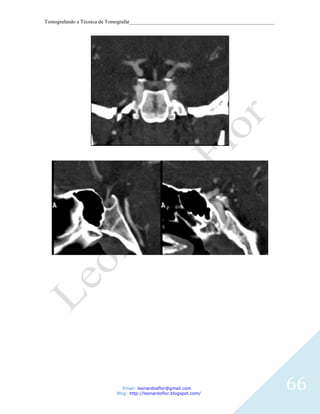

RECONSTRUCOES CORONAL E SAGITAL.

Email: leonardosflor@gmail.com

Blog: http://leonardoflor.blogspot.com/

66